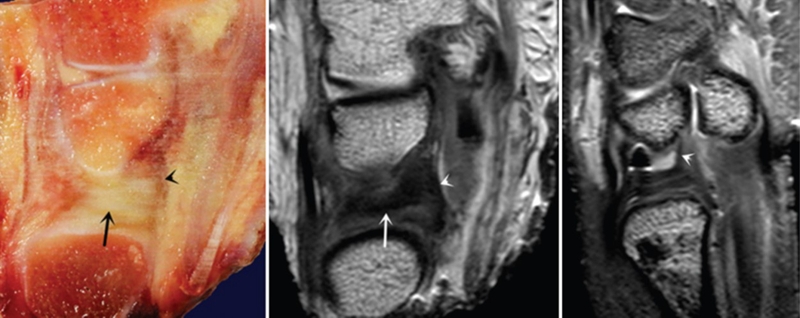

三角纤维软骨复合体(TFCC)是手腕最重要的纤维软骨-韧带复合结构,位于腕关节尺侧,分隔尺腕和远侧尺桡关节。常被称为是腕关节的“半月板”。

TFCC由以下韧带和纤维软骨组成:固有三角纤维软骨(TFC)、背侧桡尺韧带(DRUL)、掌侧尺韧带(PRUL)、尺三角韧带(UTL)、尺月韧带(ULL)、月三角韧带(LTL)、尺侧腕伸肌腱(ECU)鞘、尺侧副韧带(UCL)及半月板类似体(MH)。

半月板同系物是关节盘远侧增厚的尺侧副韧带纤维形成半月板类似体,与关节盘共同起于尺骨背侧靠近尺骨的边缘,有尸解证实其附着于豌豆骨。

ⅠA,TFCC中心穿孔,A、B三角软骨盘正常弓形低信号缺损;C轴位显示三角软骨盘中心的高信号区与D关节镜一致

ⅠB,TFCC尺侧撕裂;TFC尺侧附着处信号增高

ⅠC,尺三角韧带撕裂

ⅠD,TFC桡侧撕裂,桡侧附着处及桡尺关节处信号增高